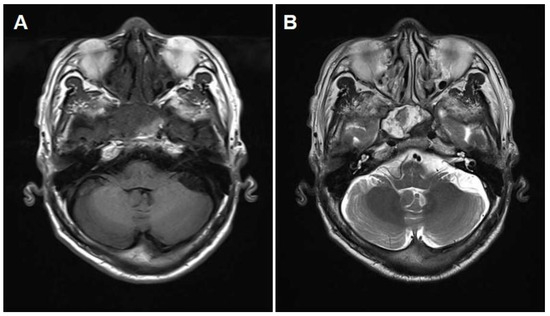

Successful Endoscopic Transsphenoidal Approach Treatment of Sphenoid Sinus Organized Hematoma Causing Visual Deficit: A Case Report

Background: Organized hematoma in the sphenoid sinus is rare, but serious complications, such as visual deficits, can occur. Three such case reports have been published previously in the literature; however, none have achieved complete recovery of the vision. Case presentation: A [...] Read more.

Background: Organized hematoma in the sphenoid sinus is rare, but serious complications, such as visual deficits, can occur. Three such case reports have been published previously in the literature; however, none have achieved complete recovery of the vision. Case presentation: A 69-year-old male patient was referred to the ear, nose, and throat department with an expansile soft tissue mass filling the right sphenoid sinus and blurry vision in his right eye. Complete mass removal was achieved by a wide opening of the sphenoid sinus via an endoscopic transsphenoidal approach, followed by cauterization of the feeding artery and coverage by a nasoseptal flap. The patient’s vision was restored after the operation, and he declared no visual symptoms until the latest follow-up (one year after the surgery). Conclusions: Complete excision with an endoscopic endonasal transsphenoidal approach can restore visual deterioration caused by a sphenoid sinus organized hematoma. Full article